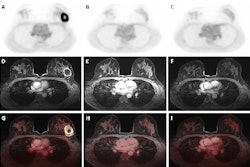

Sequences included in the study MRI protocol: (a) coronal TIRM (turbo inversion recovery magnitude) sequence, (b) coronal T1-weighted sequence, (c) axial FLAIR (fluid-attenuated inversion recovery) sequence (head only), (d) axial T2-weighted fast spin-echo sequence (HASTE), (e) axial diffusion-weighted imaging (b-value 900), (f) an axial ADC map, (g) axial T1-Dixon water-only images before contrast agent, and (h) after administration of contrast agent.All figures courtesy of Dr. Myriam Keymling et al and European Radiology

Sequences included in the study MRI protocol: (a) coronal TIRM (turbo inversion recovery magnitude) sequence, (b) coronal T1-weighted sequence, (c) axial FLAIR (fluid-attenuated inversion recovery) sequence (head only), (d) axial T2-weighted fast spin-echo sequence (HASTE), (e) axial diffusion-weighted imaging (b-value 900), (f) an axial ADC map, (g) axial T1-Dixon water-only images before contrast agent, and (h) after administration of contrast agent.All figures courtesy of Dr. Myriam Keymling et al and European Radiology

Whole-body MRI of a 39-year-old woman with LFS showing a mass in the small pelvis (white arrow) in diffusion-weighted imaging (a) and contrast-enhanced T1-weighted Dixon images (b, here: water-only image). In the coronal TIRM-sequence (c), the mass is visible, but difficult to differentiate from the intestine, emphasizing the value of diffusion-weighted imaging. Histology revealed a leiomyosarcoma.

Whole-body MRI of a 39-year-old woman with LFS showing a mass in the small pelvis (white arrow) in diffusion-weighted imaging (a) and contrast-enhanced T1-weighted Dixon images (b, here: water-only image). In the coronal TIRM-sequence (c), the mass is visible, but difficult to differentiate from the intestine, emphasizing the value of diffusion-weighted imaging. Histology revealed a leiomyosarcoma.